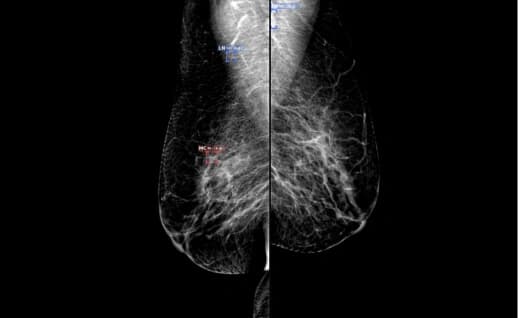

L CC R CC

L MLOR MLO

With a focus on enhancing diagnostic precision and optimizing radiologist workflows, Gamma leverages advanced AI algorithms to analyze X-rays, CT scans, and MRIs efficiently.

An AI-powered solution efficiently detects pathologies in medical imaging, including cancer, cancer nodules in the early stages. It supports X-rays, CT scans, and MRIs, reducing diagnosis time and enhancing hospital capacity by streamlining workflows.